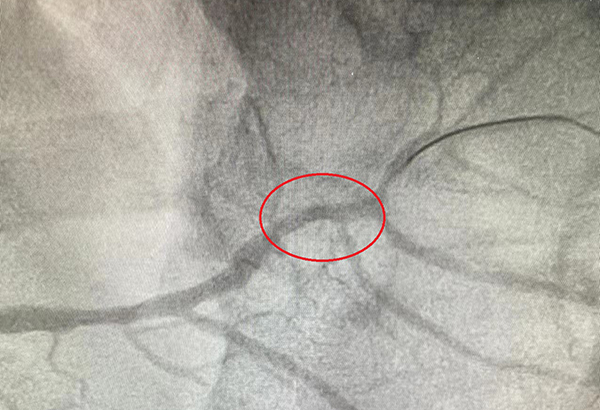

PCI术后